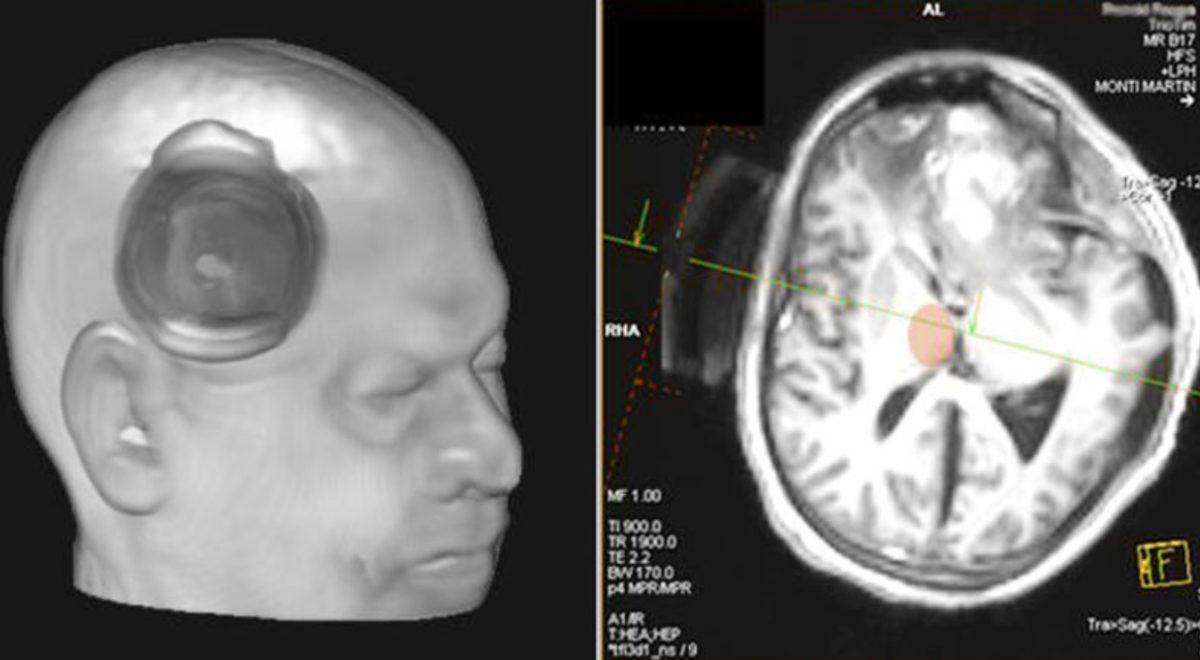

Bundan birkaç yıl önce Fransa’da 15 yıldır bitkisel hayatta olan bir hastayı uyandırmak için beynin bu bölgelerden birini uyarmanın işe yaradığını keşfettiler. Uyarılan alan hipokampüs, amigdala gibi beyin bölgeleriyle bağlantı sağlamaya yarayan vagus siniriydi. Vagus sinirinin aynı zamanda parasempatik sinir sistemini de düzenlediği düşünülüyor.

Hastayı, vagus sinirini uyararak uyandırmaya çalışan ekip, bunu 6 ay boyunca devam ettirdi. Hastanın, uyarmanın birinci ayında gözlerini açıp odadakilerin hareketlerini takip edebildiklerini fark etmişlerdi. Hasta, filmlerdeki gibi hemen kalkıp yürüyememişti. Aslında hasta, belki beynindeki ağır hasardan dolayı hiçbir zaman ne yürüyabilecekti ne de konuşabilecekti.